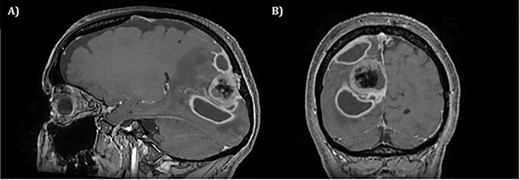

The operation was successful with a post-operative MRI within 48 h demonstrating complete resection of the tumour and resolution of the cystic lesions, but persisting intraparenchymal oedema (Fig. 3). The patient had an uncomplicated two-day stay in a neurosurgery high dependency unit postoperatively before being stepped down to the general neurosurgery ward. She was reviewed by the microbiology team and worked up for the source of infection. Blood cultures, urine cultures, CXR and transthoracic echocardiography were all negative for a source of infection. Intra-operative pus cultures isolated MSSA. The histopathology of the tumour was Meningioma WHO Grade 1 with large areas of necrosis and secondary abscess formation. She was discharged feeling well 5 days later after a satisfactory biochemical and clinical response. She was given a weaning course of steroids and a 6-week course of intravenous ceftriaxone via a PICC line as an outpatient as per microbiology advice. Ophthalmology assessment 3 months after discharge confirmed a left inferior quadrantonopia and preserved visual acuity. Repeat MRI and clinic review 8 weeks later showed no radiological residual tumour or oedema (Fig. 4), and the patient’s limb function recovered completely but had ongoing visual symptoms.

T1 weighted axial MRI postgadolinium enhancement within 48 h post-operatively. Small amount of enhancement within the surgical bed remains. Good resection margins with vasogenic oedema. This may represent a small residual. The rim-enhancing cystic lesions appear to have resolved.